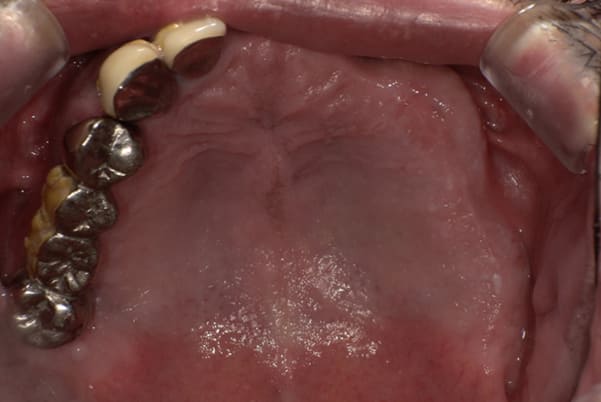

上あごに接する入れ歯に違和感がありになっていたとのことで、プラスチックが大きく削られた入れ歯をされていました。

そのため入れ歯の安定が悪く、お食事の際に入れ歯が動き、がたつきを感じられている状態でした。

前歯にバネにより見た目の問題も抱えておられました。

かみ合わせが低くなった歯を本来の高さに戻し、保険では使用できない歯に負担のかかりずらいバネで、歯の保存、審美性を確保しました。

前歯にバネを設定せず、見えない奥歯に維持力をもたせたバネを用い、またバネのかかる歯の負担軽減を目的に、被せ物は繋げることで強度を増す設計とすることで、入れ歯が動かずガタつき、審美性不良が解消されました。

部分入れ歯と対合歯

入れ歯を修理する中で、入れ歯の上あごの接触面積ではなく、厚みに対しての違和感と診断し、薄い金属を用いた従来の厚みを1/3程度にした入れ歯にすることにより違和感は消失しました。